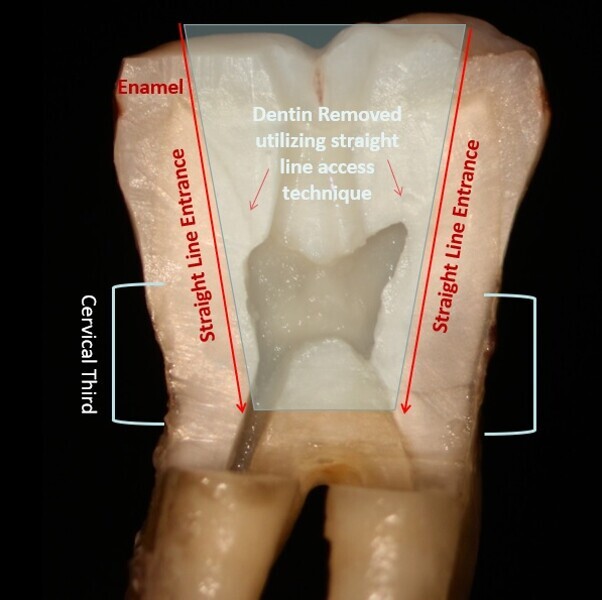

Fig. 2: Traditional endodontic access with an attempt at straight line entrance into the canal orifice typically follows a vertical path necessitating more coronal tooth structure removal.

Fig. 3: An orifice-directed access conserves more tooth structure as it follows the direction of the canal, resulting in a smaller access opening and preservation of critical tooth.